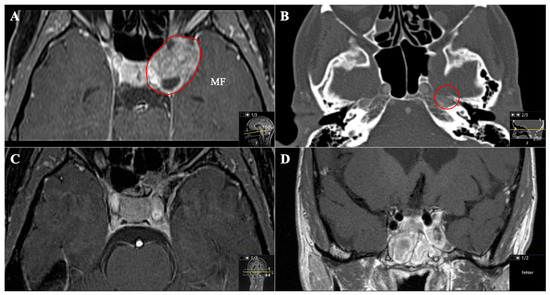

Figure 7. A 45-year-old female patient presented with left-sided visual impairment and headache. (A) Preoperative axial T1-weighted gadolinium-enhanced MRI and (B) axial CT, showing an optic-canal-compressing trigeminal schwannoma with a cystic part in Meckel’s cave in the middle fossa (MF, Samii Type A). Note how the foramen rotundum is widened (red circle). (C) Postoperative axial and (D) coronal MRI control, indicating complete resection via a transnasal endoscopic (transpterygoid) approach using a nasoseptal flap.